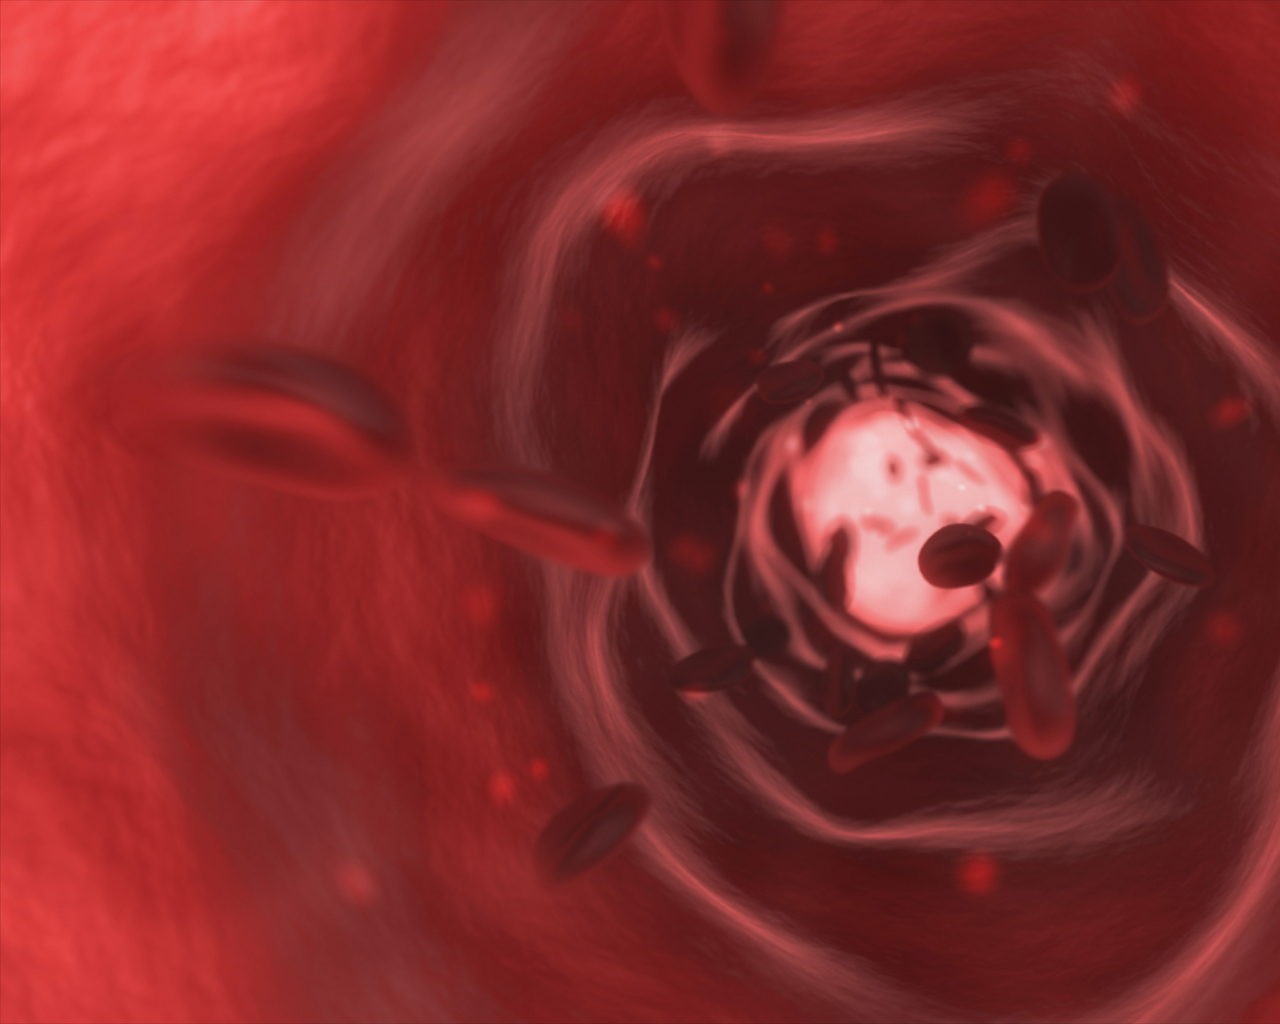

Heart attacks and strokes are still the most common causes of death today. You may already be aware of the risks and reasons why these happen, but it all sums up to the buildup of plaque in the arteries of the heart. Patients that are diagnosed with blocked arteries can undergo a stent placement in Las Piñas at the Perpetual Help Medical Center-Las Piñas.

You should know the risks and outcomes when you fail to address cardiovascular concerns. It can cause a complete blockage of the heart, which hinders the supply of the oxygen-rich blood it needs to function efficiently. This will eventually result in symptoms such as shortness of breath, chest pain, and may end up with a heart attack. Read on to see how a stent placement in the heart works and how this can be beneficial for you.

Better Blood Flow

A stent procedure can immediately improve blood flow throughout the body’s arteries. The moment the catheter reaches the damaged and blocked area of the artery, it will be placed in such a way that it restores the blood flow back to normal.